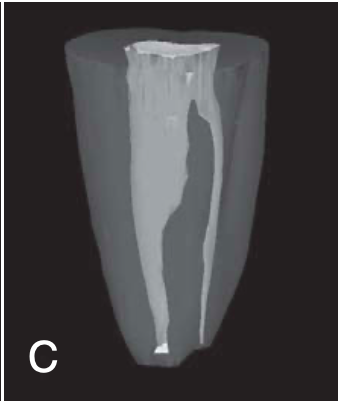

category I (C1) of C-shaped root canal

the shape is an uninterrupted “C” with no separation or division

category II (C2) of C-shaped root canal

should be no less than 60 degrees

the canal shape resembles a semicolon resulting from a discontinuation of the “C” outline

category III (C3) of C-shaped root canal

2-3 separate canals and both angles are less than 60 degrees

category IV (C4) of C-shaped root canal

only one round or oval canal is in the cross-section

category V (C5) of C-shaped root canal

no canal lumen can be observed (is usually seen near the apex only)